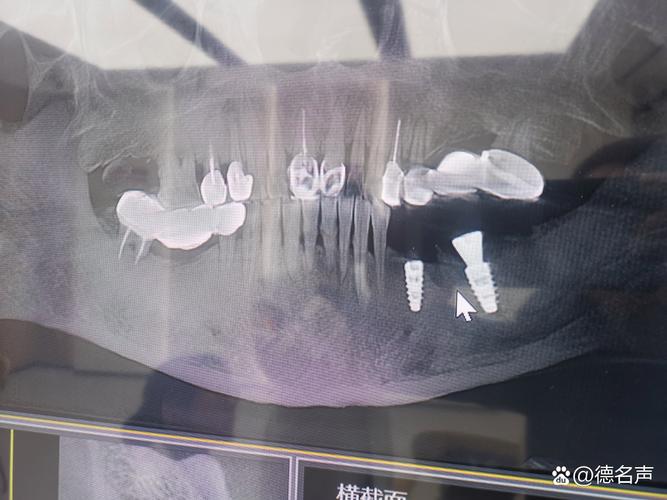

- 详细评估: 医生会通过口腔检查、X光片(全景片、根尖片)、CT扫描(锥形束CT - CBCT) 来精确评估你骨缺损的位置、范围、形态以及重要解剖结构(如下牙槽神经管、上颌窦)的位置,CBCT是制定骨增量方案的关键。

(图片来源网络,侵删)- 短种植体: 对于某些特定情况(如下颌后牙区骨高度轻度不足),医生可能会选择更短但直径更粗的种植体,短种植体的长期成功率在特定条件下也有很好的保障,但需要严格评估适应症。